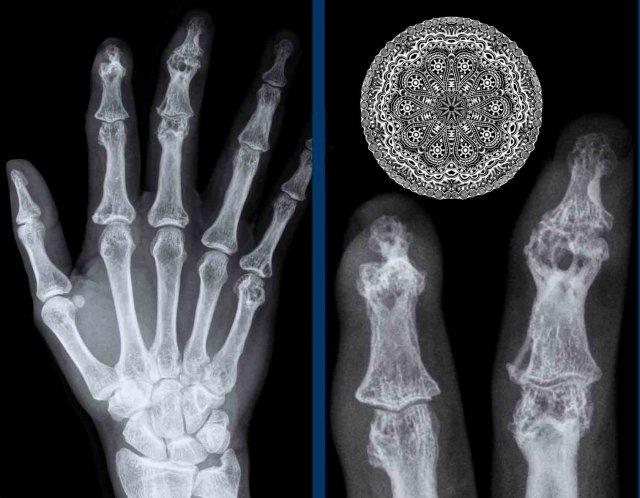

Vôi hóa mô mềm

Vôi hóa mô mềm lan rộng tại các đốt ngón xa ở bệnh nhân xơ cứng bì.

Lưu ý các vôi hóa cạnh đầu xa xương trụ (mũi tên).

Không có dấu hiệu tổn thương sụn khớp.

Vôi hóa mô mềm kín đáo nhưng thô ráp tại phần xa nhất của ngón tay ở bệnh nhân xơ cứng bì.

Không ghi nhận tiêu xương đầu chi hay các dấu hiệu bất thường khác.

Tiêu xương đầu chi trong Xơ cứng bì

Tiêu xương đầu chi nặng tại đầu ngón tay của ngón 1-3 ở bệnh nhân xơ cứng bì (mũi tên). Lưu ý hiện tượng tiêu hủy mô mềm ở phần xa.

Tiêu xương đầu chi là dấu hiệu X-quang chỉ sự phá hủy xương tại các đốt ngón xa, xảy ra ở 6–65% bệnh nhân xơ cứng bì.

Các biến đổi mạch máu và giảm mật độ mao mạch làm suy giảm cung cấp oxy cho mô, và tình trạng thiếu oxy kết quả có thể góp phần kích hoạt hủy cốt bào.

Có nhiều bệnh lý khác nhau có thể gây tiêu xương đầu chi, bao gồm viêm khớp vảy nến, nhiễm trùng, bệnh Raynaud và chấn thương nhiệt.

U hạt dạng ren (Lace-like granulomas)

Nhiều tổn thương xương trên một bệnh nhân sarcoid.

Các tổn thương tiêu xương khá điển hình và được mô tả có dạng ren hoặc dạng bè xương.

Một khi đã nhận ra hình ảnh này, bạn sẽ dễ dàng nhận diện nó trong các trường hợp khác.

Hình ảnh cho thấy một tổn thương tiêu xương ở đầu xa xương quay (mũi tên xanh) với phá hủy xương bè và vỏ xương trên một bệnh nhân sarcoid.

Có phá hủy xương ở cả hai phía của khớp liên đốt ngón tay cái kèm theo lan rộng ra ngoài xương của mô u hạt (mũi tên đen).